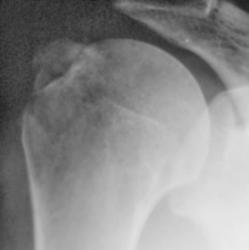

Травма. пациент направлен хирургом в рентгеновский кабинет для рентгенографии плечевого сустава. Были произведены рентгенограммы в двух проекциях. Могу представить, увы, только изображение в прямой проекции.

"Перелом-отрыв бугорка плечевой кости", так любят его наши травматологи, так и называют.

Соглашусь с коллегой Ореховым! Оторвался бугорок!

Ну, и по всей видимости, перелом, без смещения костных отломков.

Насчет линейной тени (две медиальные стрелки) - думаю, не перелом это, закрытая зона роста.

Однозначно, линия, указанная стрелками, это бывшая ростковая зона.

Вот то, что отмечено желтыми стрелочками на последней серии снимков - и есть отрыв большого бугорка. Такой большооооой отрыв большоооооооого бугорка.

Мое мнение, что анатомическая шейка плечевой кости абсолютно интактная! Пациент достаточно молод.